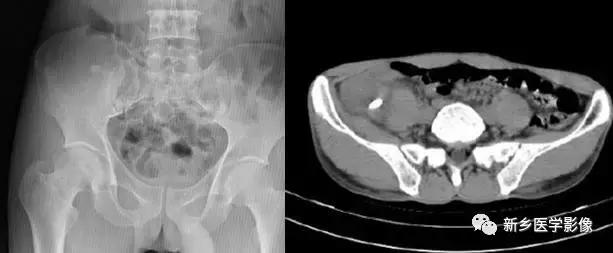

8

子宫平滑肌瘤(纤维瘤)

主要位于盆腔内,表现为不均一的点状钙化

15

前列腺钙化灶